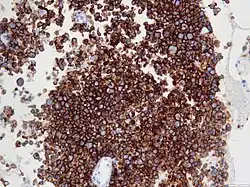

Micrograph of an anaplastic large-cell lymphoma. H&E stain.

Immunohistochemistry for CD30

ALK-positive ALCL is diagnosed by histological and immunological examinations of involved tissues, typically lymph nodes. These tissues have lymphoma-like infiltrates that have variable numbers of ALCL "hallmark" cells, i.e. cells with kidney- or horseshoe-shaped nuclei that strongly express CD30 as detected by immunohistochemistry and an ALK fusion protein as detected by fluorescence in situ hybridization.[11] These cells are scattered throughout the infiltrates. WHO classifies these infiltrates into 5 patterns: a common pattern consisting of large variably shaped cells with large nuclei that typically contain multiple nucleoli (60–70% of cases); a small-cell pattern consisting of small to medium-sized neoplastic cells with clear cytoplasm and "hallmark" cells that are concentrated around small blood vessels (5–10% of cases); a lymphohistiocytic pattern consisting of small neoplastic cells along with abundant histiocytes (10% of cases); a Hodgkin's-like pattern in which the architecture resembles the nodular sclerosis pattern of Hodgkin lymphoma (3% of cases); and a composite pattern consisting of two or more of the just described patterns (15% of cases).[9] Detection of circulating autoantibody against ALK supports the diagnosis.[10] Individuals with low levels of these autoantibodies are at an increase risk of relapsing after treatment.[9]